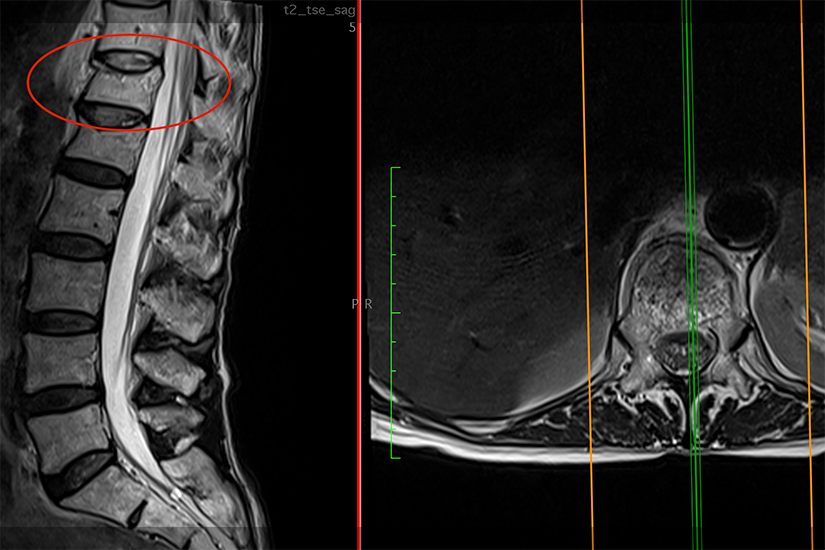

Dr. Robert Clement a preluat cazul și după investigațiile imagistice și consultul clinic general a propus pacientei intervenția de kyphoplastie pentru ambele vertebre tasate. „Am explicat pacientei care este problema, de ce a apărut durerea bruscă și intensă. Examenul RMN la nivelul coloanei vertebrale a relevat existența unei tasări vertebrale considerabile, de aproximativ 50%, la nivelul ultimei vertebre de la nivel toracal, acest lucru explicând îndeaproape simptomatologia pacientei.”

Indicația de kyphoplastie urmează după o serie de investigații imagistice specifice. Scopul acestora este de a arăta cu exactitate afectarea osoasă a vertebrelor și gradul de afectare și de a elimina hernia de disc ca posibilă cauză a durerii. Sunt utilizate examenele cu raze X, tomografia computerizată (CT) sau scanările prin rezonanță magnetică (RMN). Acestea identifică exact leziunile și confirmă prezența fracturilor vertebrale. Dacă se confirmă diagnosticul de osteoporoză, pacientul va face și o investigație suplimentară, respectiv osteodensitometrie (DEXA).